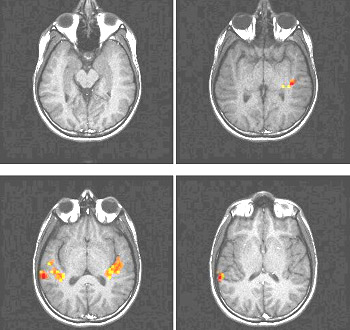

Volver al menú principal de IRMf